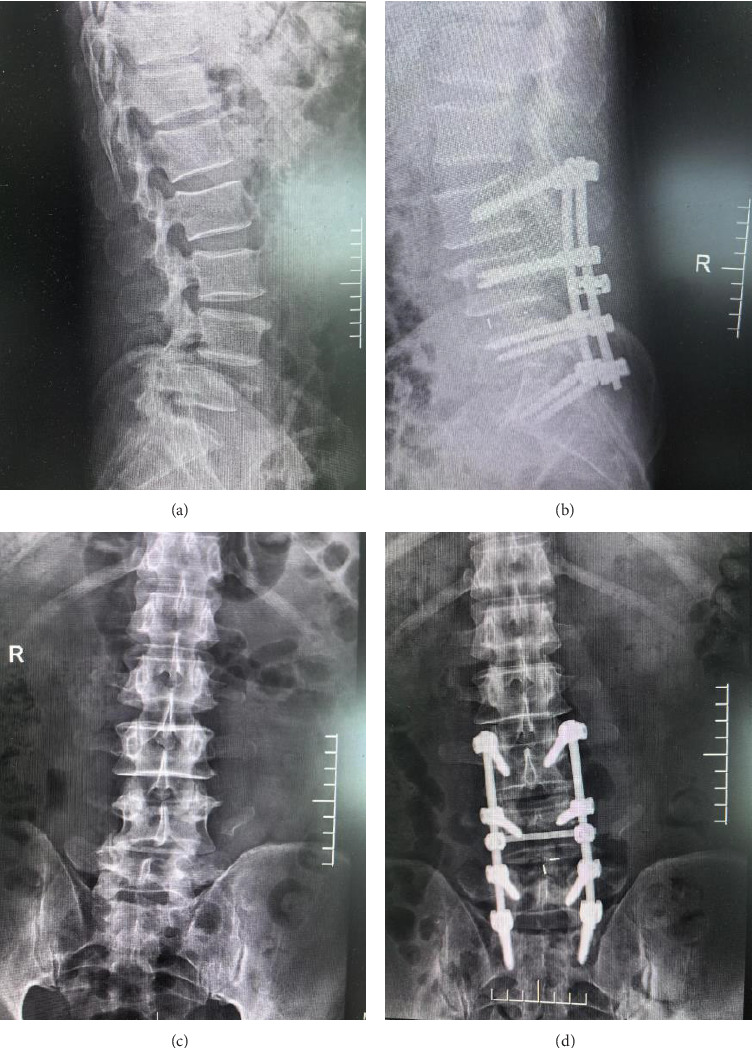

Objective: This study evaluates the effectiveness and timeliness of posterior decompression and internal fixation in the emergency management of thoracolumbar fractures complicated by spinal cord injuries. Methods: We retrospectively analyzed 40 patients treated at our hospital from January 2019 to February 2022. Each patient underwent posterior decompression and internal fixation, with preoperative and postoperative assessments including vertebral body height, American Spinal Injury Association (ASIA) score, Visual Analog Scale (VAS) score, and urodynamic indices. Results: Postoperative improvements were noted in vertebral body height, with anterior and posterior heights increasing to 12.82 (± 1.23) mm and 3.21 (± 0.64) mm, respectively, and kyphosis angle improving to 14.26 (± 0.32). Significant enhancements were also observed in motor (from 40.78 [± 4.32] to 59.86 [± 1.37]) and sensory (from 45.98 [± 3.20] to 66.92 [± 1.28]) function scores, and a reduction in VAS score from 6.89 (± 0.78) to 1.78 (± 0.32). Urodynamic measurements showed increased maximum urine flow and detrusor pressure postintervention. All surgical wounds healed within two weeks without significant complications. Conclusion: Posterior decompression and internal fixation significantly improve spinal stability, pain, motor, and sensory functions in patients with thoracolumbar fractures and spinal cord injuries, demonstrating its effectiveness and clinical utility.